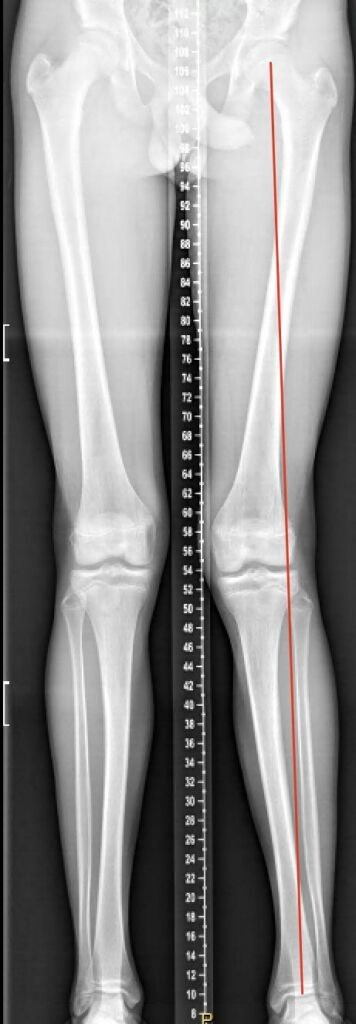

Valgus

Hier is duidelijk te zien dat de belasting juist meer aan de buitenkant zit, na de correctie precies door het midden.